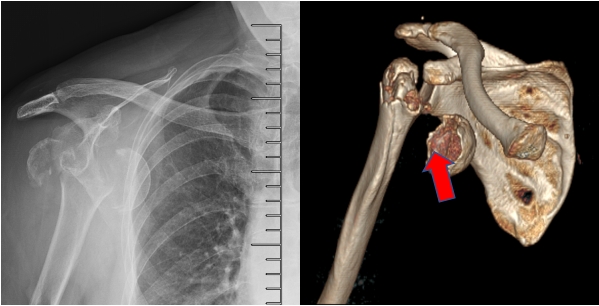

患者申阿姨,今年68岁,近日在家中不慎摔倒,就是这一摔,造成了申阿姨的右肩剧烈疼痛。申阿姨的家人当即将她送到我院急诊外科就诊,影像检查显示情况复杂。杨小海主任受邀会诊,检查发现,由于患者原本就患有严重的骨质疏松,所以即便受到并不算太严重的冲击,也导致了她右侧肱骨近端粉碎性骨折,还发生了肱骨头脱位。这样复杂的骨折合并脱位,无法通过一般的骨折复位内固定解决问题。

患者肱骨近端粉碎性骨折,肱骨头移位明显